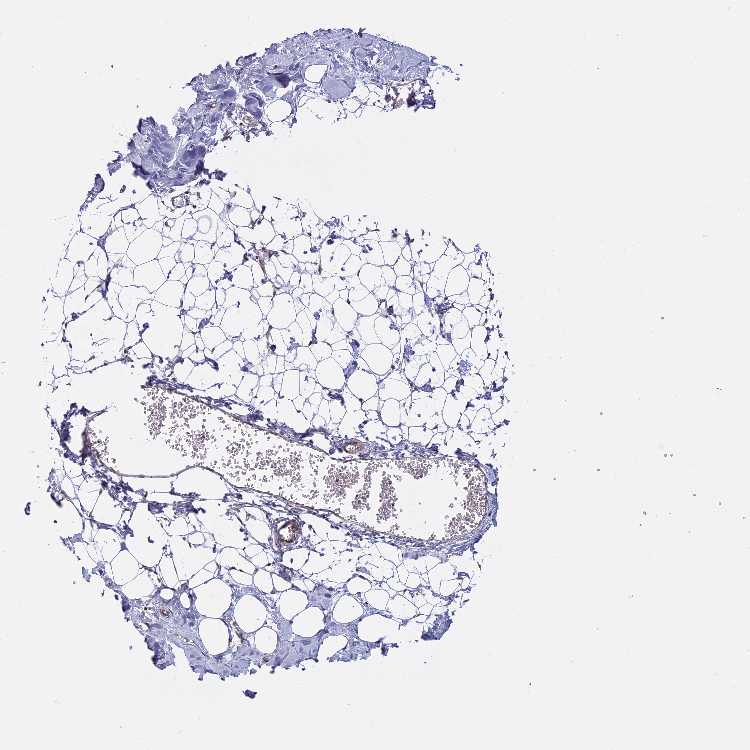

BREAST - Antibody stainingi

Antibody staining in the annotated cell types in the current human tissue is reported as not detected, low, medium, or high, based on conventional immunohistochemistry profiling in selected tissues. This score is based on the combination of the staining intensity and fraction of stained cells.

Each image is clickable and will lead to virtual microscopy that enables deeper exploration of all samples and also displays staining intensity scores, fraction scores and subcellular localization as well as patient and tissue information for each sample.

Antibody HPA040759Antibody HPA040869

Adipocytes Not detectedMedium

Glandular cells Not detectedMedium

Myoepithelial cells MediumLow